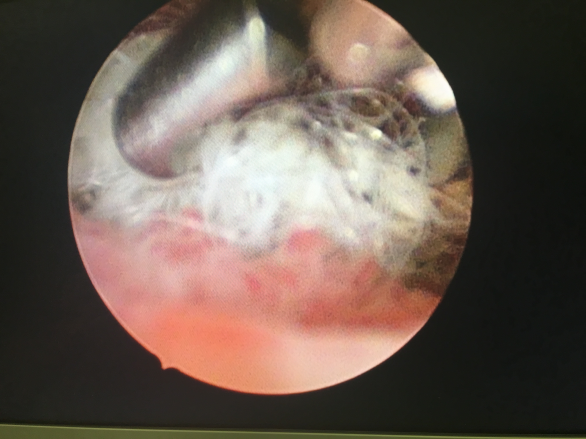

2016年9月27日我院门诊接诊一位4岁小女孩,父亲和姑妈陪她来看病,3个月前小女孩出现阴道血性分泌物,在当地医院对症治疗,效果不佳,吴衡慧主任在门诊接诊了小女孩,行彩超检查提示阴道内一异常回声,吴主任给她安排了宫腔镜检查。9月28日,小女孩在父亲和姑妈的陪同下来到了宫腔镜手术室,史素娥主任接诊了小女孩,结合症状和辅助检查考虑阴道异物可能性大,同时也不能排除肿瘤可能,向患者家属详细交代病情后手术开始,在全麻下,史素娥主任谨慎细心的操作,通过阴道内镜检查,竟然发现毛球状似丝绵样异物藏于阴道内,异物与周围组织粘连紧密,触之出血,术中考虑与直肠关系密切,担心直接强力牵拉损伤周围脏器,请妇科张菊新主任会诊后制定进一步治疗方案,最终在张菊新主任指导下史素娥主任在阴道内镜引导下异物钳逐次将一根根细丝多次取出才清理干净。女童外阴、处女膜、阴道黏膜均无裂伤破损,既保护了幼女处女膜的完整无缺,也保障了儿童的身心健康。感谢我们的麻醉和护理团队,整个过程都是在没有插管的静脉全麻下行阴道内镜查及异物钳取出,手术过程清晰无创,效果良好,完满成功。在宝宝开始有朦胧的性意识时,怎样保护他们的“小屁屁”呢?